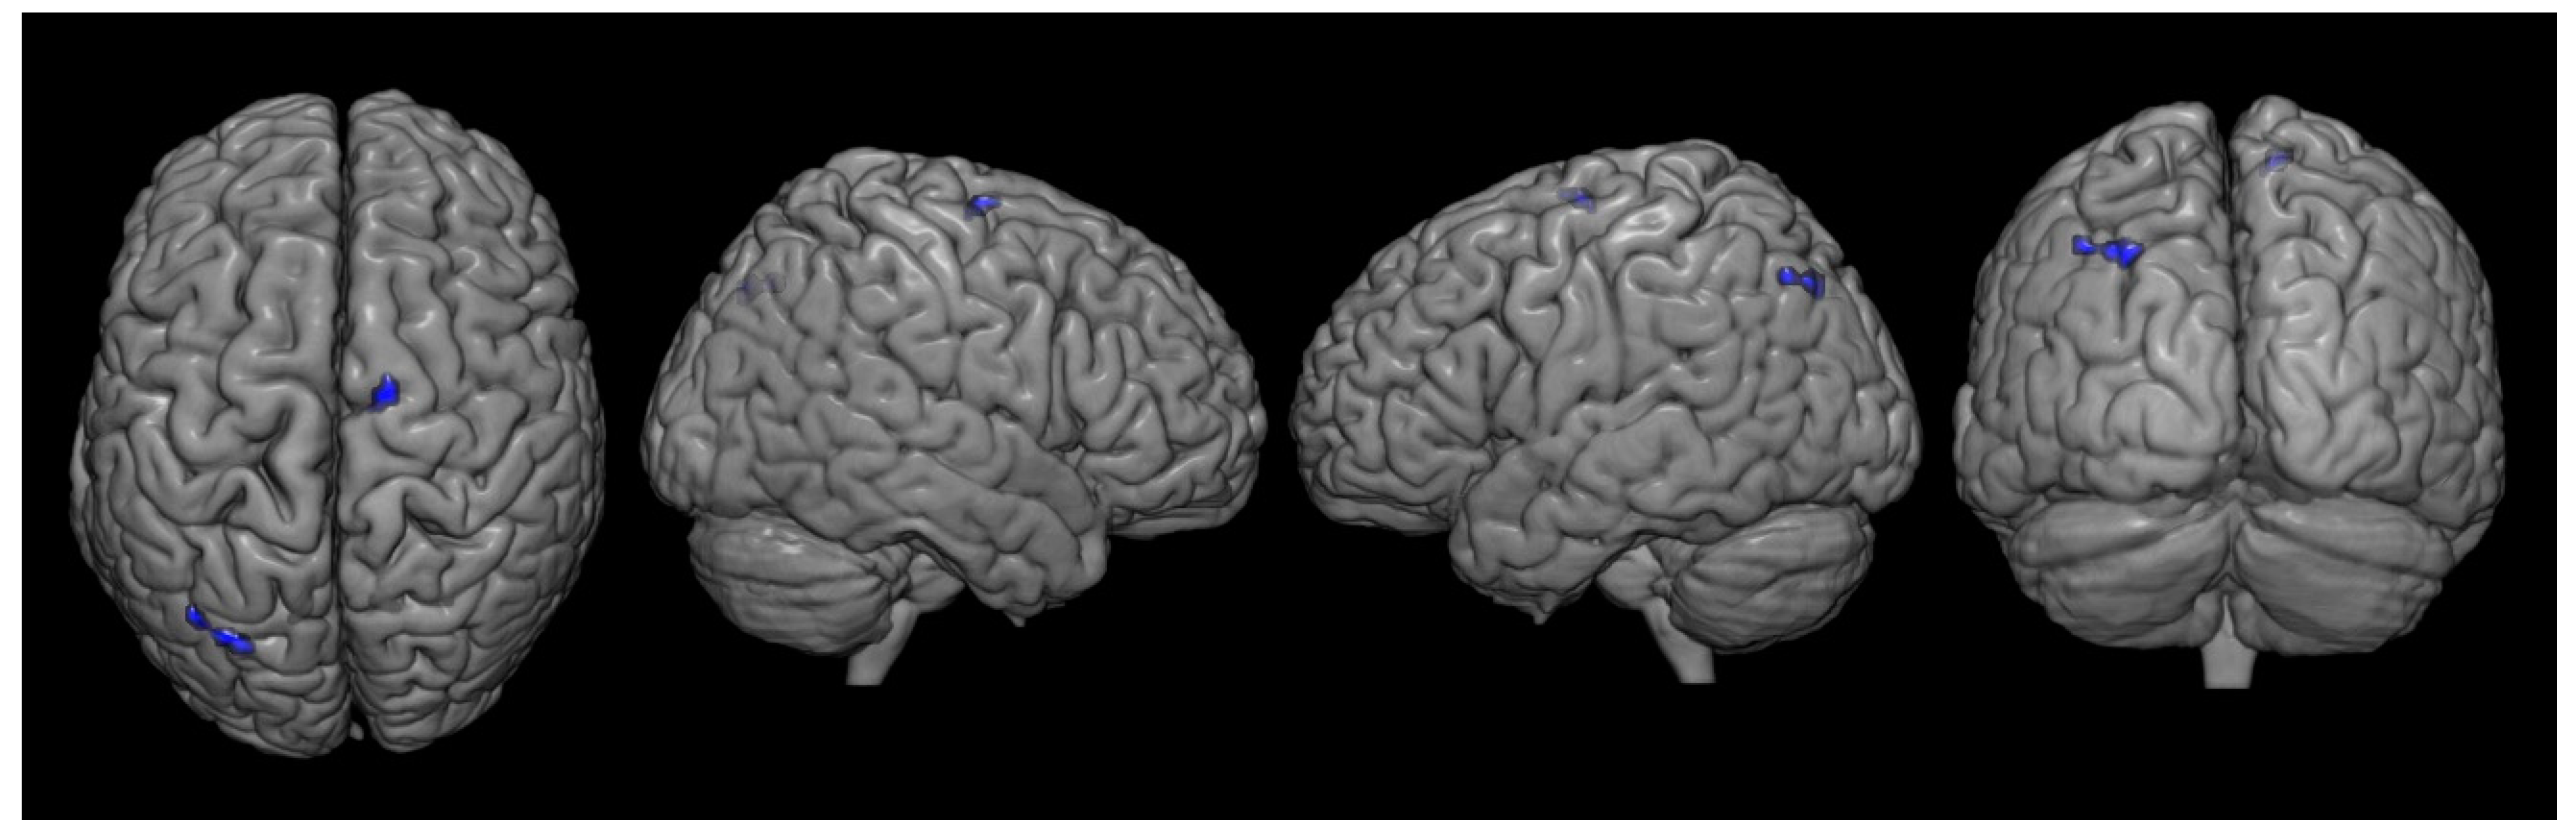

| Metabolism | Area | Coordinate | t Score | z Score | Cluster | ||

|---|---|---|---|---|---|---|---|

| x | y | z | |||||

| Decreased | Ipsilesional Supplementary Motor Cortex | 10 | −10 | 66 | 4.83 | 3.47 | 73 |

| Contralesional angular gyrus | −28 | −74 | 44 | 4.52 | 3.33 | 171 | |